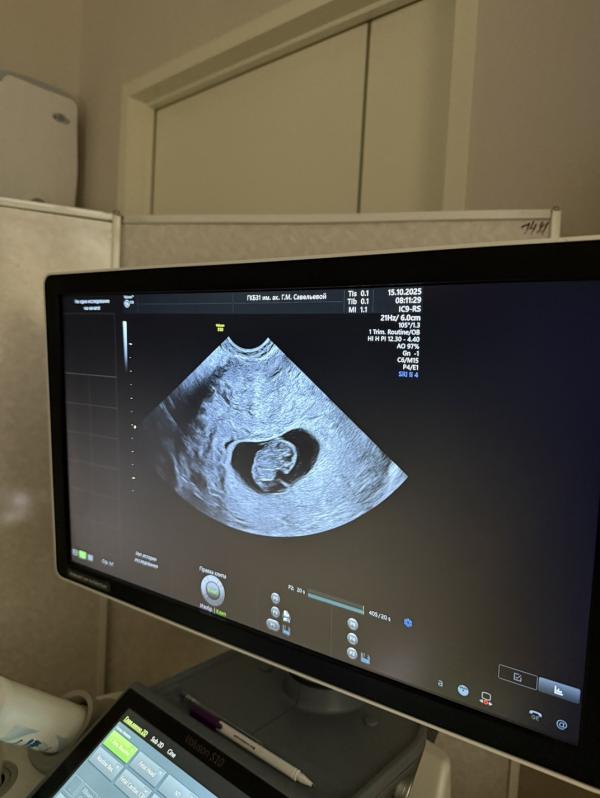

Встала на учёт в центр Женского здоровья, срок 8.4) будем получать молочную кухню, первый скрининг 9 ноября)